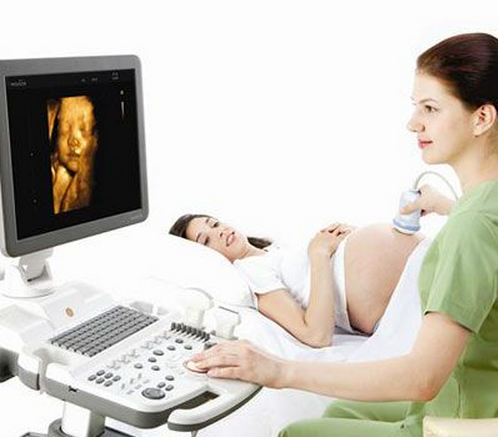

三维彩超怎么看男女 教你三维彩超看性别

三维彩超看生男生女准确吗?不少备孕中的爸爸妈妈想要知道这个问题的答案。自己所在的地区没有四维彩超设备,因此想通过三维彩超来看看自己的胎儿会是男孩还是女孩。一般在三个月以后就可以看清楚了。三维彩超怎么看生男生女呢?